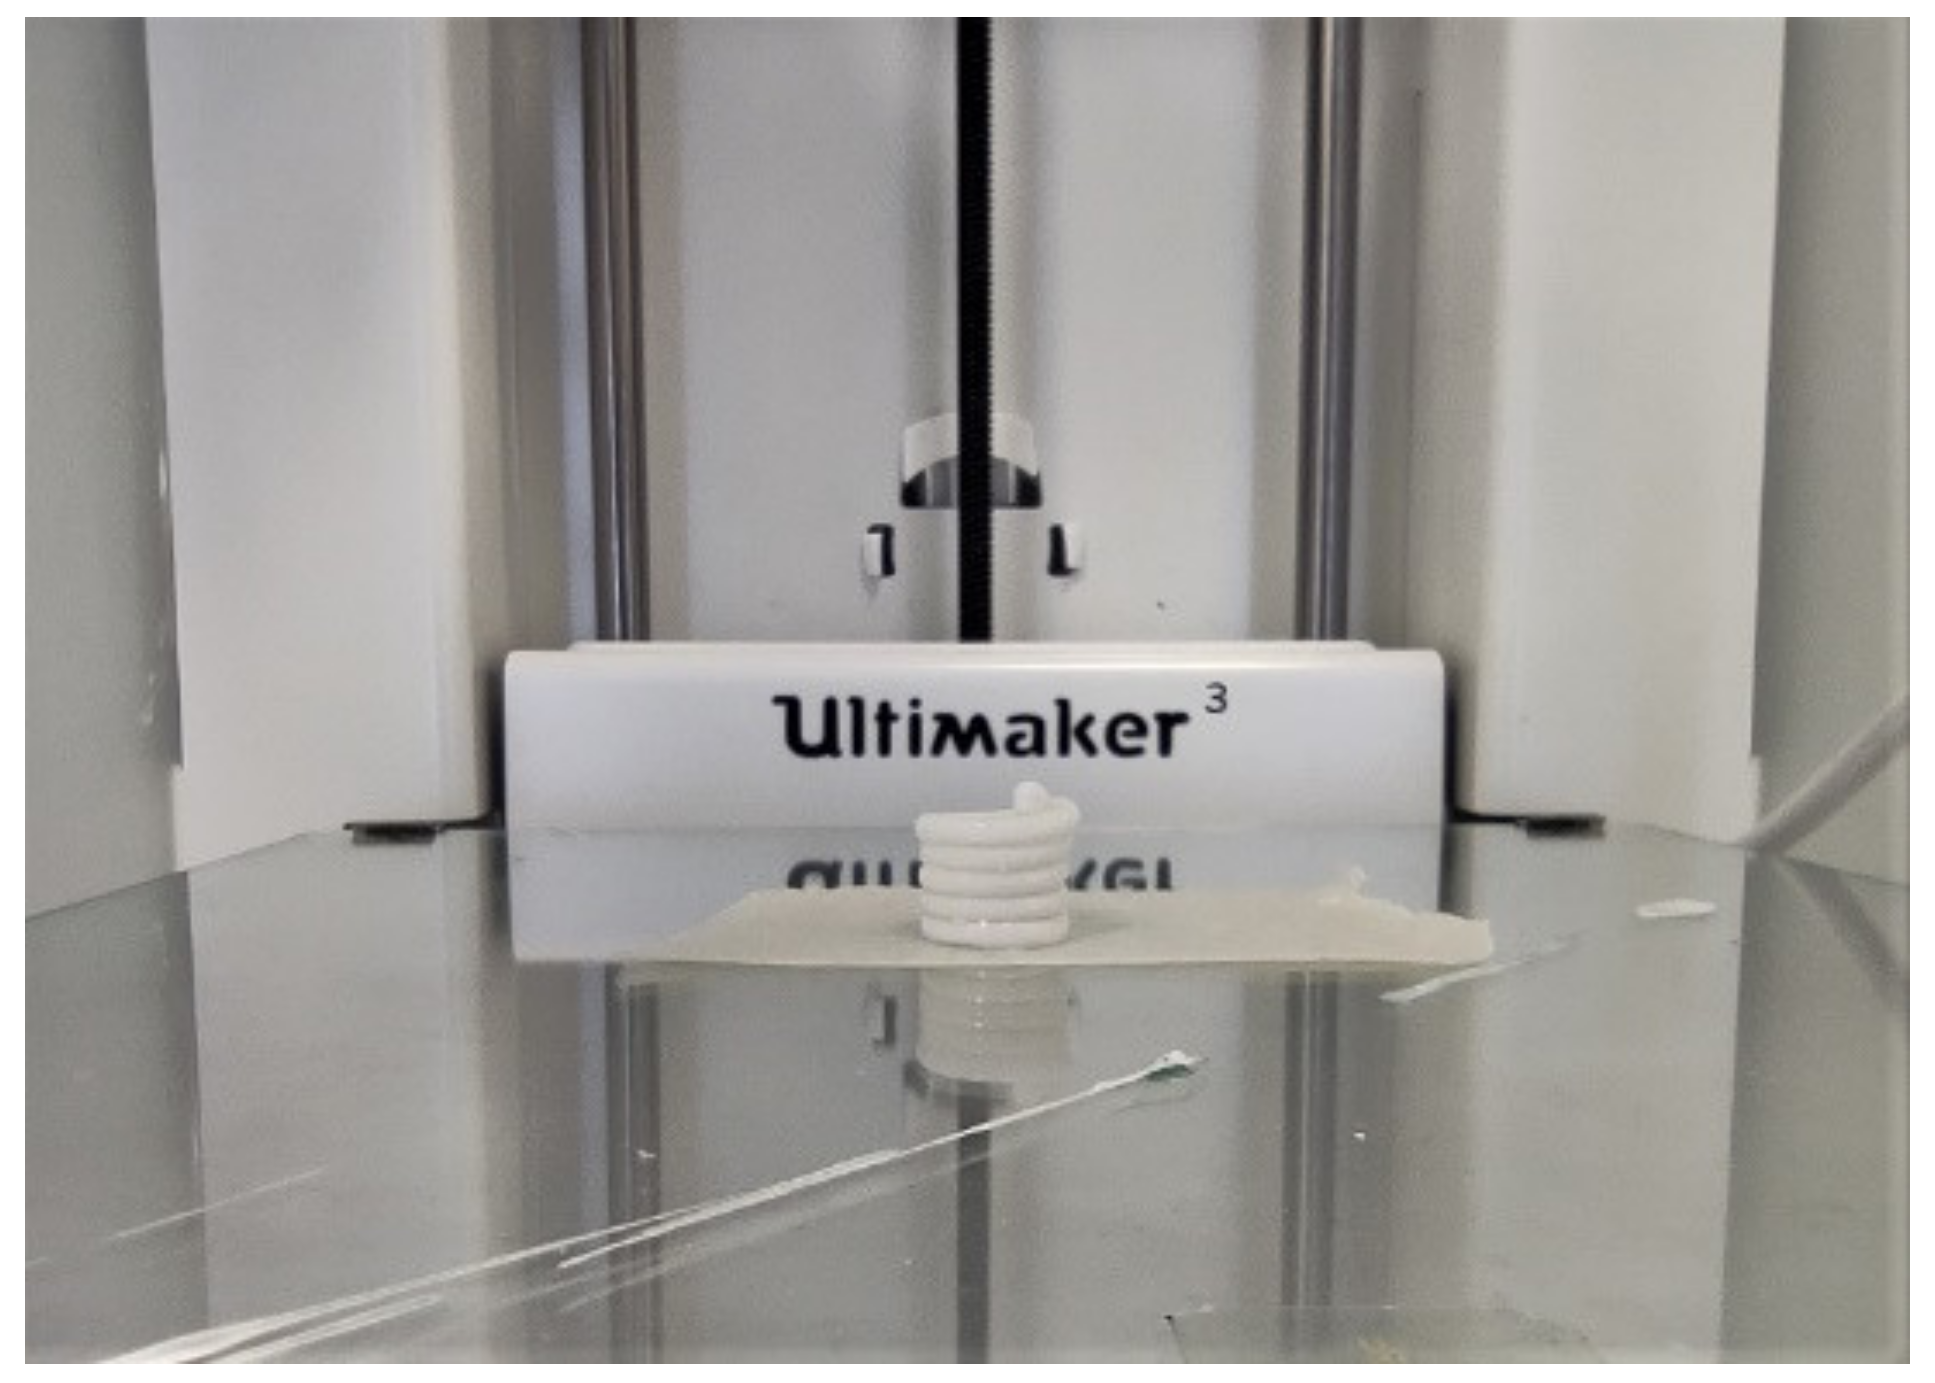

2.3. Design, Development, and Production of DDS

4.2.3. Design, Development, and Production of DDS